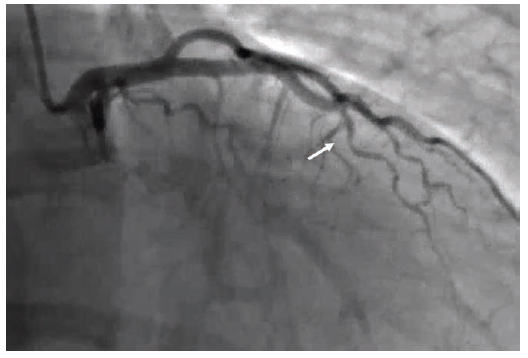

Patient 1 is a woman in her 50s, with chronic back pain, hypertension, and remote history of a transient ischemic attack (TIA). She presented to the emergency department with chest pain and elevated high sensitivity troponins >80,000 and was taken to the cath lab. She was found to have type II spontaneous coronary artery dissection in the mid to distal left anterior descending (LAD) coronary artery (Figures 1-2; Video 1). The right coronary artery (RCA) was normal. Of note, the patient had a similar presentation more than 1 year ago with high sensitivity troponins >16,000. The angiogram was normal (Figure 3; Video 2).

Patient 2 is a woman in her 40s who is 4 weeks postpartum and presented with chest pain, accelerated hypertension, and elevated high sensitivity troponins >32,000. In the cath lab, she was found to have type II spontaneous coronary artery dissection of an obtuse marginal (OM) branch (Figure 4; Video 3) with a small branch cutoff.